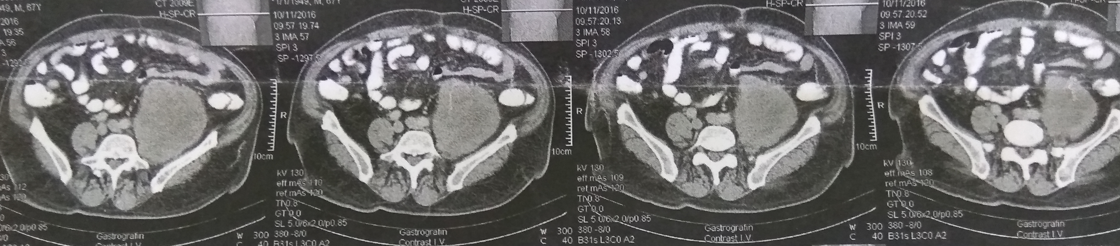

Ένας 68χρονος ασθενής , εισήχθη σε επαρχιακό νοσοκομείο , παραπονούμενος για οξύ κοιλιακό άλγος , δυσχέρεια αναπνοής και πτώση της αρτηριακής πίεσης. Μετά την αρχική αναζωογόνηση , έγινε αξονική τομογραφία κοιλίας , η οποία ανέδειξε την παρουσία , ευμεγέθους , πολυλοβωτής , χαμηλής πυκνότητας , εξεργασίας μαλακών ιστών , στην περιοχή του αριστερού λαγονίου βόθρου , ενδεικτικών διαστάσεων 10 Χ 6.8 εκ . που ανέρχονταν προς τα επάνω , μέχρι τον κάτω πόλο του αριστερού νεφρού , ενώ κατέρχονταν όπισθεν των έξω λαγονίων αγγείων , μέχρι το ύψος των κοκκυγικών σπονδύλων ( ενδεικτική κεφαλουραία διάμετρος 16.4 εκ . ) . Τα υπόλοιπα όργανα της κοιλίας ήταν φυσιολογικά , όπως φυσιολογική ήταν και η εκτελεσθείσα σε 2ο χρόνο αξονική τομογραφία θώρακος , χωρίς την ανάδειξη μεταστατικών εστιών στο ήπαρ ή στους πνεύμονες . Μετά την σταθεροποίηση του , ο ασθενής ανέφερε ότι βίωνε ένα αμβλύ άλγος στην αριστερή οσφύ , τους τελευταίους 2 μήνες , το οποίο απέδιδε στην δυσκοιλιότητα . Από το ατομικό και οικογενειακό ιατρικό ιστορικό , δεν υπήρξε κάτι το άξιο λόγου . Κατά την κλινική εξέταση , διαπιστώθηκε εκσεσημασμένη διάταση κοιλίας , με σύσπαση αριστερά χωρίς περιτοναισμό και βύθιους εντερικούς ήχους . Υπήρξε αδυναμία ψηλάφησης μαζών . Η Hb ήταν 8 gr , οπότε και μεταγγίστηκε με δύο μονάδες ερυθρών κυττάρων . Ο χρόνος προθρομβίνης ήταν φυσιολογικός , όπως ήταν οι ηπατικές δοκιμασίες και οι λοιπές βιοχημικές εξετάσεις . Τα επίπεδα των κατεχολαμινών , της κορτιζόλης και της αλδοστερόνης ήταν εντός των φυσιολογικών ορίων . Την επόμενη ημέρα , με απαίτηση της οικογένειας του , ο ασθενής διακομίστηκε στην κλινική μας για περεταίρω αντιμετώπιση . Εικόνα 1 . CT Scan Κοιλίας . Τεράστια οπισθοπεριτοναική μάζα αριστερά . ( Αρχείο κος Β . Πενόπουλος ) . Αφού λάβαμε υπ’ όψιν μας , το αρνητικό για σοβαρές παθήσεις ιατρικό ιστορικό του ασθενούς , την παρουσία ενός εξαιρέσιμου οπισθοπεριτοναικού όγκου ο οποίος αιμορράγησε ( πτώση Α . Π . και Hb ) , την απουσία εγκλωβισμού / διήθησης κρίσιμων αγγείων από τον όγκο , την απουσία μεταστάσεων , την επαπειλούμενη απόφραξη του αριστερού ημικόλου και την ανάγκη μιας αξιόπιστης διάγνωσης , αποφασίσαμε να προχωρήσουμε στην εκτέλεση ερευνητικής λαπαροτομίας . Μετά την διάνοιξη της κοιλίας , διαπιστώσαμε την παρουσία αιμοπεριτοναίου , το οποίο προφανώς προεκλήθη από την ρήξη και την αιμορραγία του αγγειοβριθούς οπισθοπεριτοναικού όγκου . Μετά την αφαίρεση περίπου 1 λίτρου αίματος και θρόμβων , αποκαλύφθηκε μία εύθρυπτη , σκουρόχρωμη μάζα , διαστάσεων 10.5 Χ 7.2 εκ . , κάτωθεν του κάτω πόλου του αριστερού νεφρού , με ασαφή όρια , η οποία ήταν συμπεφυμένη στερεά με τον αριστερό ψοίτη μύ . Τα περιφερικά αγγειακά στελέχη ήταν ελαφρώς διατεταμένα ως εκ της πιέσεως της μάζας αλλά δεν παρατηρήθηκαν διακυμάνσεις της αρτηριακής πίεσης κατά την διάρκεια των χειρισμών του όγκου . Με προσεκτικούς χειρισμούς και παρά την αιμορραγική διάθεση του ασθενούς , κατέστη δυνατή η πλήρης αφαίρεση του όγκου χωρίς μείζονα αιμορραγία , συμπεριλαμβανομένων των τμημάτων όπισθεν των έξω λαγονίων αγγείων , en bloc μετά του κατιόντος κόλου και του σιγμοειδούς τα οποία θεωρήθηκαν διηθημένα από τον όγκο κατά συνέχεια ιστού - εγχείρηση κατά Hartmann . Εικόνα 2 . Αγγειοσάρκωμα . Διατομή παρασκευάσματος . ( Αρχείο κος Β . Πενόπουλος ) . Εικόνα 3 . Λεπτομέρεια εσωτερικού αγγειοσαρκώματος . ( Αρχείο κος Β . Πενόπουλος ) . Εικόνα 4 . Συρρικνωμένο κατιόν και σιγμοειδές κόλον . Κόκκινα βέλη . Διήθηση του παχέος εντέρου κατά συνέχεια ιστού . ( Αρχείο κος Β . Πενόπουλος ) . Εικόνα 5 . «Θυγατρικοί» όγκοι προσκολλημένοι προιερά . ( Αρχείο κος Β . Πενόπουλος ) . Η ιστοπαθολογική εξέταση , αποκάλυψε πως η οπισθοπεριτοναική μάζα , ήταν ένας κακοήθης όγκος , με ιστική νέκρωση στο εσωτερικό της νεοπλασίας . Τα καρκινικά κύτταρα ήταν επιθηλιοειδή κύτταρα με προφανή κυτταρική ατυπία και έντονη μιτωτική δραστηριότητα . Η ανοσοιστοχημική εξέταση , ανέδειξε θετική αντίδραση στην πανκυτοκερατίνη , βιμεντίνη και CD31 . Αντίθετα δεν υπήρξε αντίδραση σε διάφορους δείκτες , όπως το αντιγόνο της επιθηλιακής μεμβράνης , S100 , τον παράγοντα μεταγραφής SOX-10 , το μαύρο-45 του ανθρωπίνου μελανώματος , το melan-A , την ποδοπλανίνη , το CD117 , τον παράγοντα μεταγραφής-1 του θυρεοειδούς , την χρωμογρανίνη Α και την ακτίνη των λείων μυικών ινών . Τέλος , ο δείκτης του αντιγόνου Ki-67 , ήταν περίπου 50% . Εικόνα 6 . Επιθηλιοειδή καρκινικά κύτταρα , με προφανή κυτταρική ατυπία και μιτωτικές εικόνες . ( Αρχείο κος Β . Πενόπουλος ) . Εικόνα 7 . Ανοσοιστοχημική εξέταση-CD31 (+). ( Αρχείο κος Β . Πενόπουλος ) . Ο ασθενής είχε ομαλή μετεγχειρητική πορεία και εξήλθε του Νοσοκομείου μας 10 ημέρες αργότερα . Προ της εξόδου του , εκτιμήθηκε από ογκολόγο και προγραμματίστηκε να λάβει συμπληρωματική θεραπεία . Παρέμεινε ελεύθερος συμπτωμάτων , με καλή ποιότητα ζωής για μεγάλο χρονικό διάστημα . Απεβίωσε 18 μήνες αργότερα , μετά την εμφάνιση πολλαπλών μεταστάσεων στους πνεύμονες .